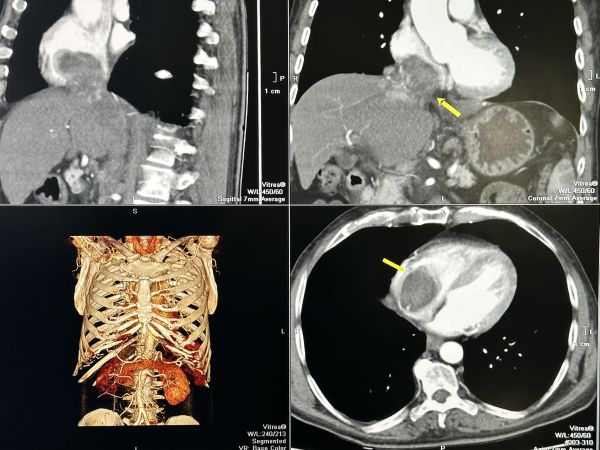

Кардиохирурзите от болница „Чирков“ отстраниха огромни туморни образувания от сърцето и черния дроб на 60-годишен пациент, съобщиха от лечебното заведение. Туморът с размери 7 на 9 сантиметра е ангажирал и изпълнил почти изцяло кухината на дясното предсърдие на сърцето и е застрашавал да запуши белодробните артерии и белия дроб.

След постъпването на пациента в лечебното заведение е направен скенер, от който се установяват злокачествените образувания в кухините на сърцето и наличието на две огромни туморни огнища в черния дроб. Туморът се разпространява и в коремната област като обхваща и запушва прехода на вена, преминаваща през черния дроб. Размерът на туморното образувание в този участък е с дължина 17 сантиметра и широчина 3 см.